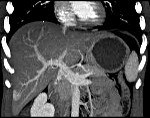

При проведении компьютерной томографии выявляется хорошо отграниченное образование, накопление контрастного вещества в области гиперплазии. МРТ дает аналогичные результаты: гиперинтенсивность контрастирования в артериальную фазу и гипоинтенсивность - в венозную. Неинвазивные методики обладают специфичностью только при классическом типе нодулярной гиперплазии печени. Высокой информативностью при проведении дифференциальной диагностики с другими гиперваскулярными образованиями обладает сцинтиграфия печени. В затруднительных случаях может быть выполнена ангиография, но данный метод также неспецифичен.